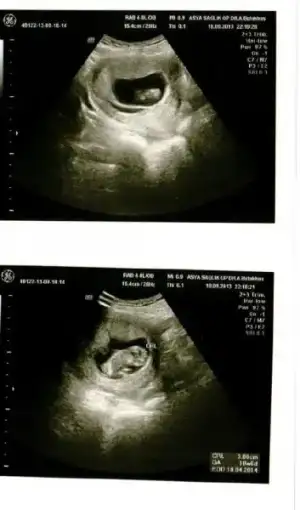

ilk 12 haftada 5 kio almıştım hatırlarsınız...sonracıma yürüyüşe başladım, yogaya başladım, karbonhidratı azaltıp, tatlı vb. seylerin sadece tadına bakmaya başladım ve sonuç 8 haftada yalnızca 1 kilo aldım. yani 68 kilo ile başlayan hamilelik serüvenim 74 ile devam ediyor. hedef artık her ay 1-1,5 kilo almak.son ay da 2 kilo olabilir. ki normal olanı da bu zaten.